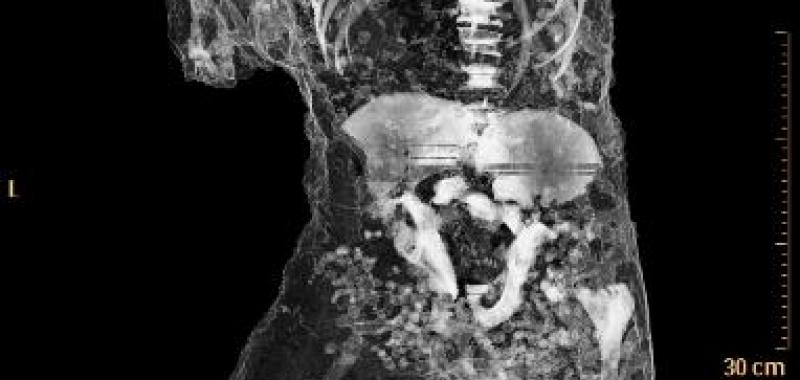

Por primera vez, un grupo de moldes de yeso de Pompeya ha sido sometido a tomografías axiales computerizadas (TAC), a partir de las que ha sido posible determinar la edad, las patologías médicas, los hábitos alimentarios y el estilo de vida de los habitantes de la ciudad arrasada por el Vesubio en el 79 d.C.

El objetivo del estudio radiológico ha sido obtener imágenes del interior de los cuerpos que quedaron conservados en ceniza durante la erupción del volcán, y que luego fueron rellenados con yeso con el propósito de preservar su integridad.

Asimismo, han sido realizados relieves en tres dimensiones de todos los cuerpos mediante técnicas digitales de vanguardia que permiten obtener datos sobre cómo ha variado su estado de conservación en el tiempo.